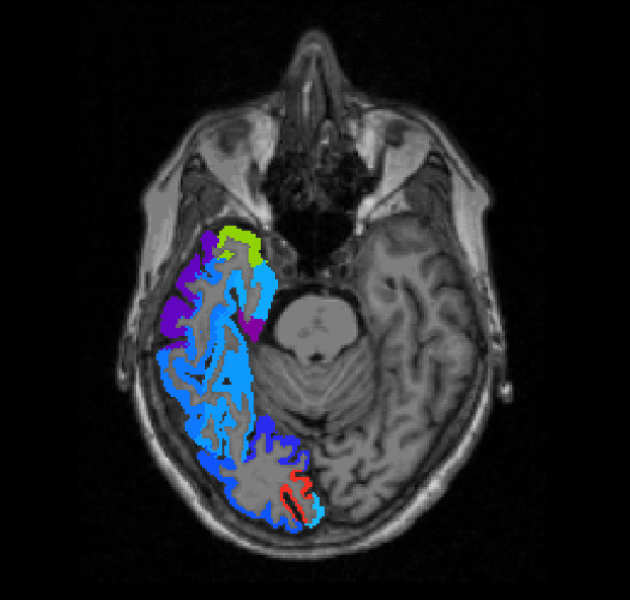

Brain tumour classification through machine learning

We are developing new machine learning tools to aid clinicians in diagnosing brain tumours through MRI and digital pathology.

We are developing new machine learning tools to aid clinicians in diagnosing brain tumours through MRI and digital pathology.

Multiparametric analysis of brain tumours

We are investigating the integration of different imaging (DCE-MRI, DWI-MRI, DSC-MRI and PET) techniques for the characterization of tumour tissue.

We are investigating the integration of different imaging (DCE-MRI, DWI-MRI, DSC-MRI and PET) techniques for the characterization of tumour tissue.